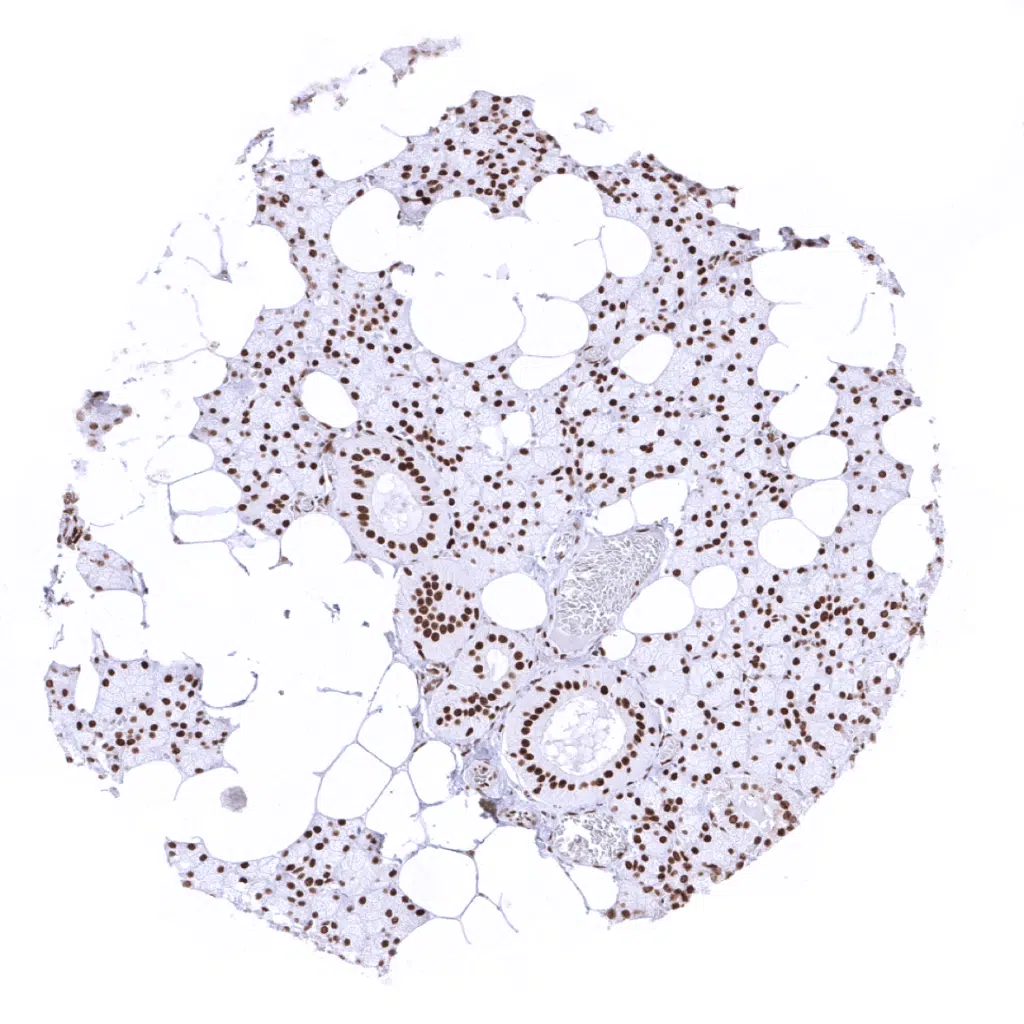

Thyroid gland